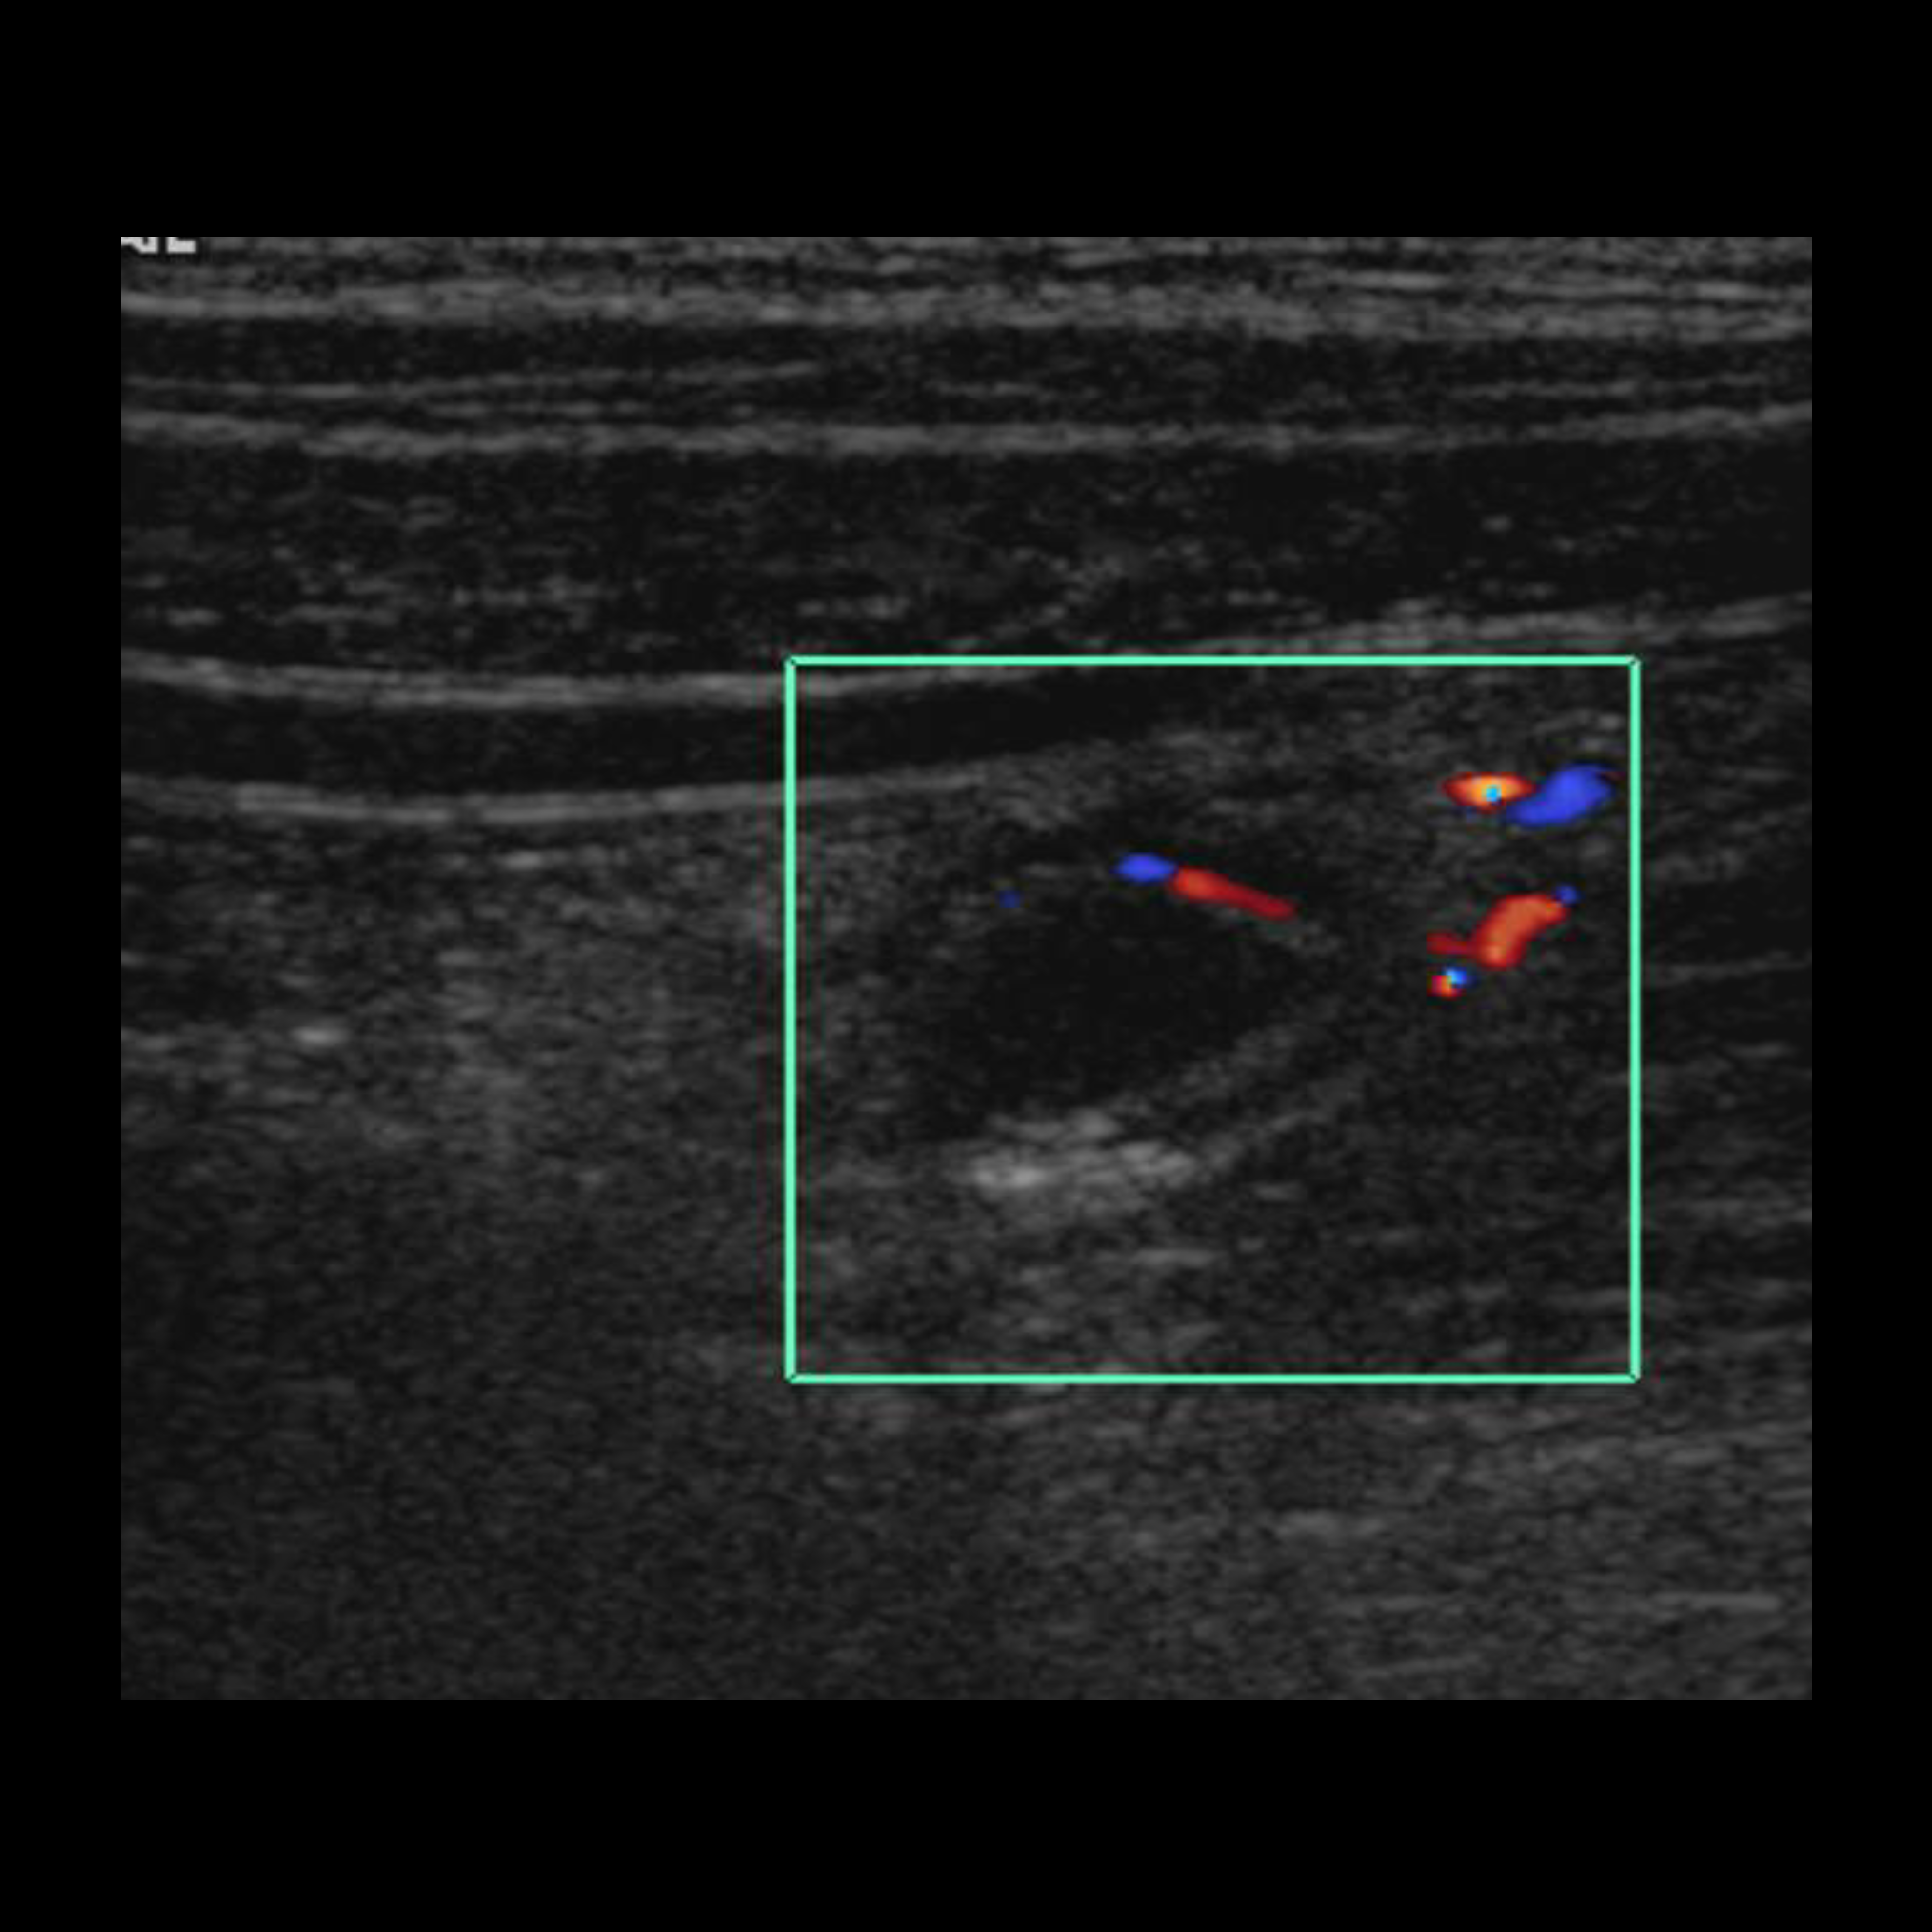

Appendicitis 4

1 cm appendicitis with hyperemia and appendicolith